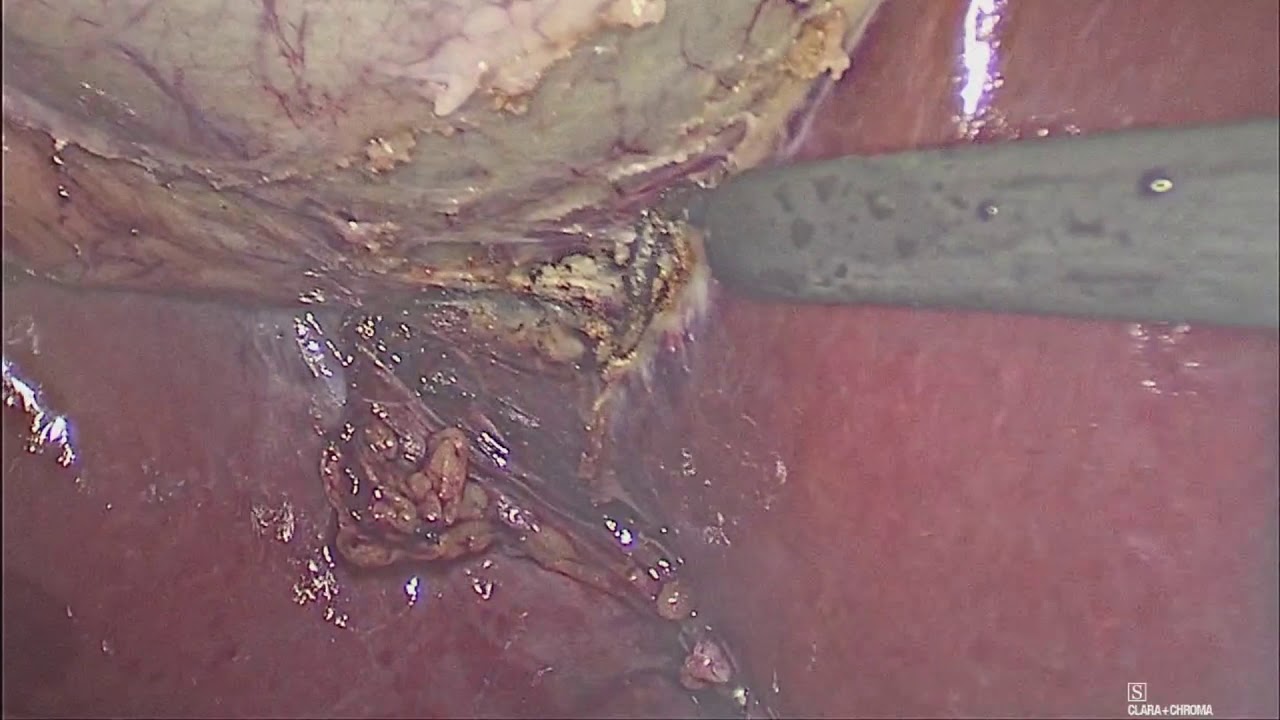

• Cirugía laparoscópica

• Cirugía gastrointestinal

Cirugía General y cirugía en trasplante renal. Hospital Mac Norte